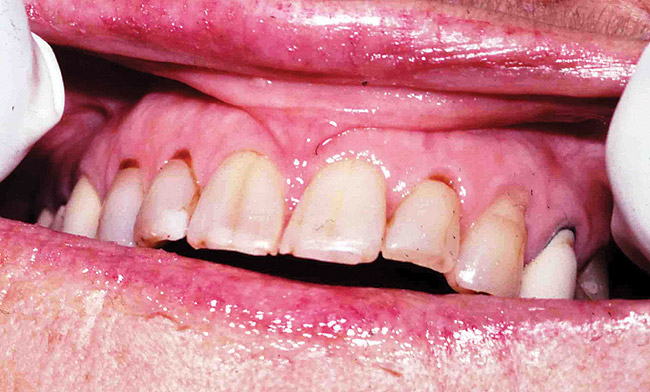

Figure 2 Dental caries is usually seen in cervical and incisal surfaces.

Figure 2

Saliva aids for oral cavity cleansing, swallowing, taste, speech, and digestion could be compromised in patients with salivary gland hypofunction. The oral mucosa may appear dry and friable. The tongue may appear dry and fissured (Figure 1). Dental caries, plaque accumulation, gingivitis, and periodontitis are common in patients with significant salivary gland hypofunction (Figure 2). Infections, such as oral candidiasis (Figure 3), and enlargement of salivary glands from sialadenitis are seen commonly in patients with moderate-to-severe salivary gland hypofunction (Figure 4). Difficulty in mastication and swallowing also may indicate advanced salivary gland hypofunction19 and can contribute to poor nutrition.20 Denture retention may become difficult because of the lack of saliva12 (Table 3).